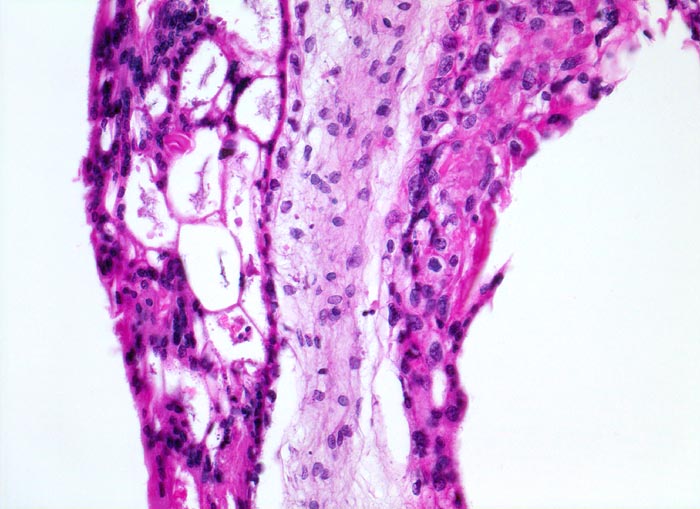

Makroskopisch ist die Plazenta deutlich grösser als erwartet für das Schwangerschaftsalter. Sie ist diffus von bis 2cm grossen Zottenblasen durchsetzt, welche nach Kollaps jedoch der makroskopischen Entdeckung entgehen können. Beim Aufschwemmen in Flüssigkeit entfalten sich die Blasen wieder. Mikroskopisch sind die Zotten aufgrund einer grobblasigen pseudozystischen Hohlraumbildung im Zottenstroma überwiegend grosskalibrig. Im Zottenstroma sind nur ganz vereinzelt Kapillaren nachweisbar. Im Gegensatz zu hydropisch geschwollenen Zotten im Sinne eines Regressionsphänomens zeigen die Zotten bei Blasenmole zusätzlich eine zirkumferentielle Hyperplasie von Synzytio- und Zytotrophoblast mit fakultativer Zellatypie. Bei herdförmiger Mole (> 3725) sind diese Veränderungen nur in einem Teil der Plazentarzotten ausgeprägt.

• Stark vergrösserte und verplumpte Plazentarzotten.

• Hydropisch umgewandeltes Zottenstroma ohne Gefässe mit Ausbildung von pseudozystischen Hohlräumen (Blasen)

• Trophoblastinklusionen und Kerntrümmer im Zottenstroma.

• Überschiessend proliferiertes Trophoblastepithel, teils in der gesamten Zirkumferenz der Zotten mit deutlichen Kernatypien. Kein Embryo.

• Deziduafragmente